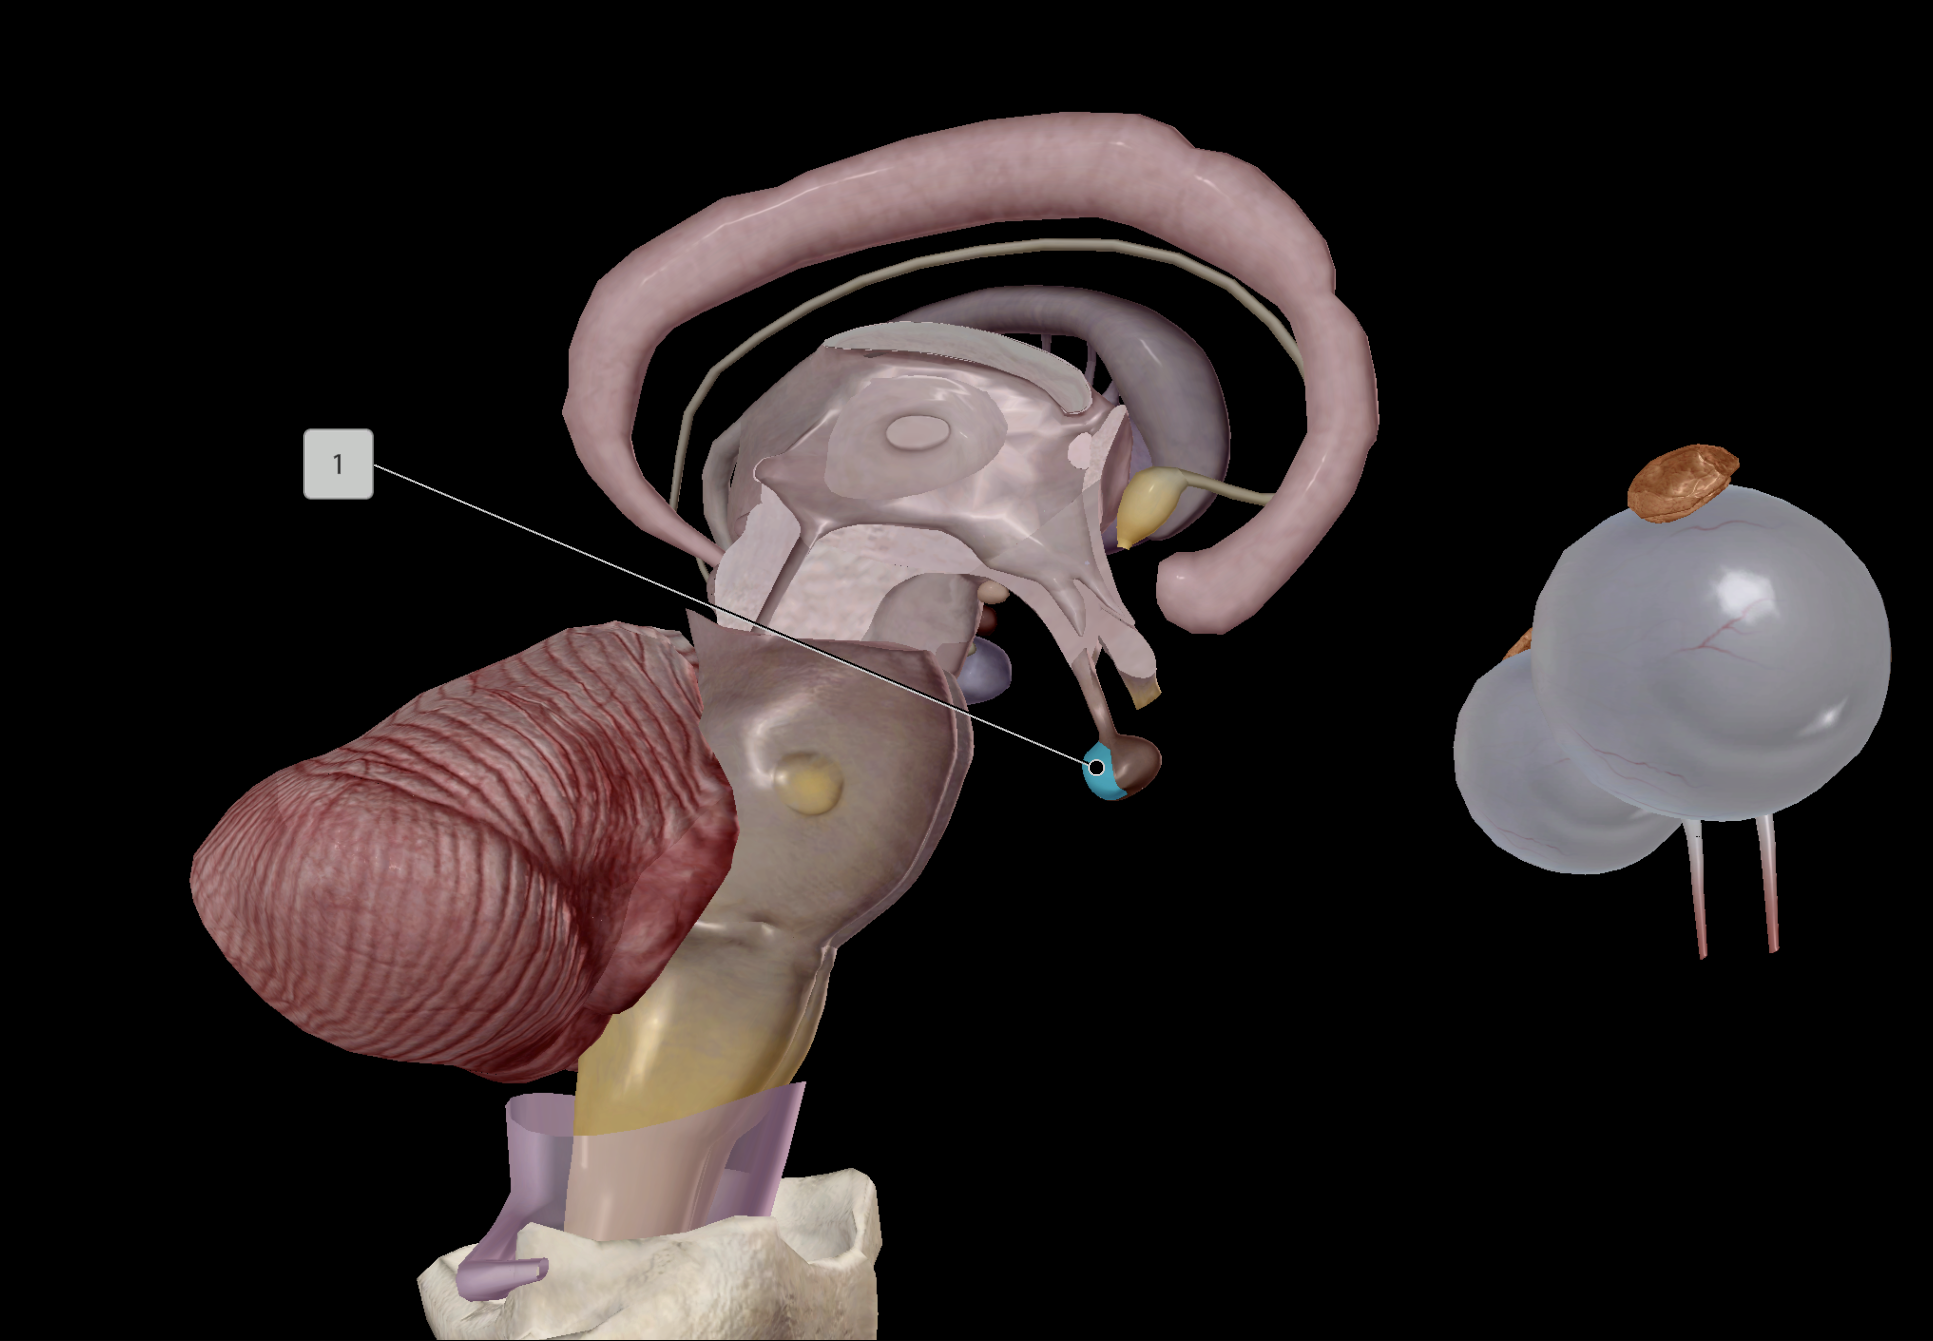

Hypothalamus